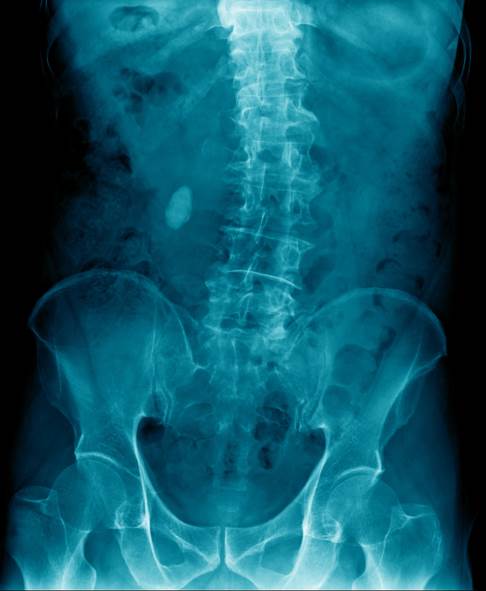

Bei der körperlichen Untersuchung zeigt sich in der Regel eine deutliche seitliche Verbiegung der Wirbelsäule. Eine Skoliose liegt ab einer seitlichen Verkrümmung der Wirbelsäule von 10 Grad vor. Diese wird anhand des Cobb-Winkels gemessen, den der Rückenspezialist im Röntgenbild bestimmen kann. Die Prognose bei frühzeitiger Therapie ist meist recht gut.

Bei Skoliosen im Lendenbereich sind die beiden Dreiecke zwischen der Taille und den seitlich am Rumpf herunterhängenden Armen (= Taillendreiecke) unterschiedlich ausgebildet. Es besteht ein Lendenwulst auf der krümmungsabgewandten Seite. Mithilfe der Röntgenuntersuchung kann der Arzt die Form und das Ausmaß der Skoliose beurteilen.

Die Stärke der Krümmung der Wirbelsäule ermittelt er über eine besondere Winkelmessung nach Cobb. Darüber hinaus beurteilt der Arzt den Torsionsgrad (Grad der Verdrehung) anhand der Pedikelschatten im Röntgenbild. Als Pedikel bezeichnet der Mediziner den Übergang zwischen Wirbelkörper und Wirbelbogen auf der Rückseite des Wirbels. In unserer Praxis wird mittels einer laseroptischen, dreidimensionalen Wirbelsäulenrekonstruktion die Gesamtausprägung der Skoliose auf das kleinste Detail berechnet. Darüber hinaus können auf diese Weise Röntgenbilder und damit die Strahlenbelastung bei Kindern erheblich eingespart werden.